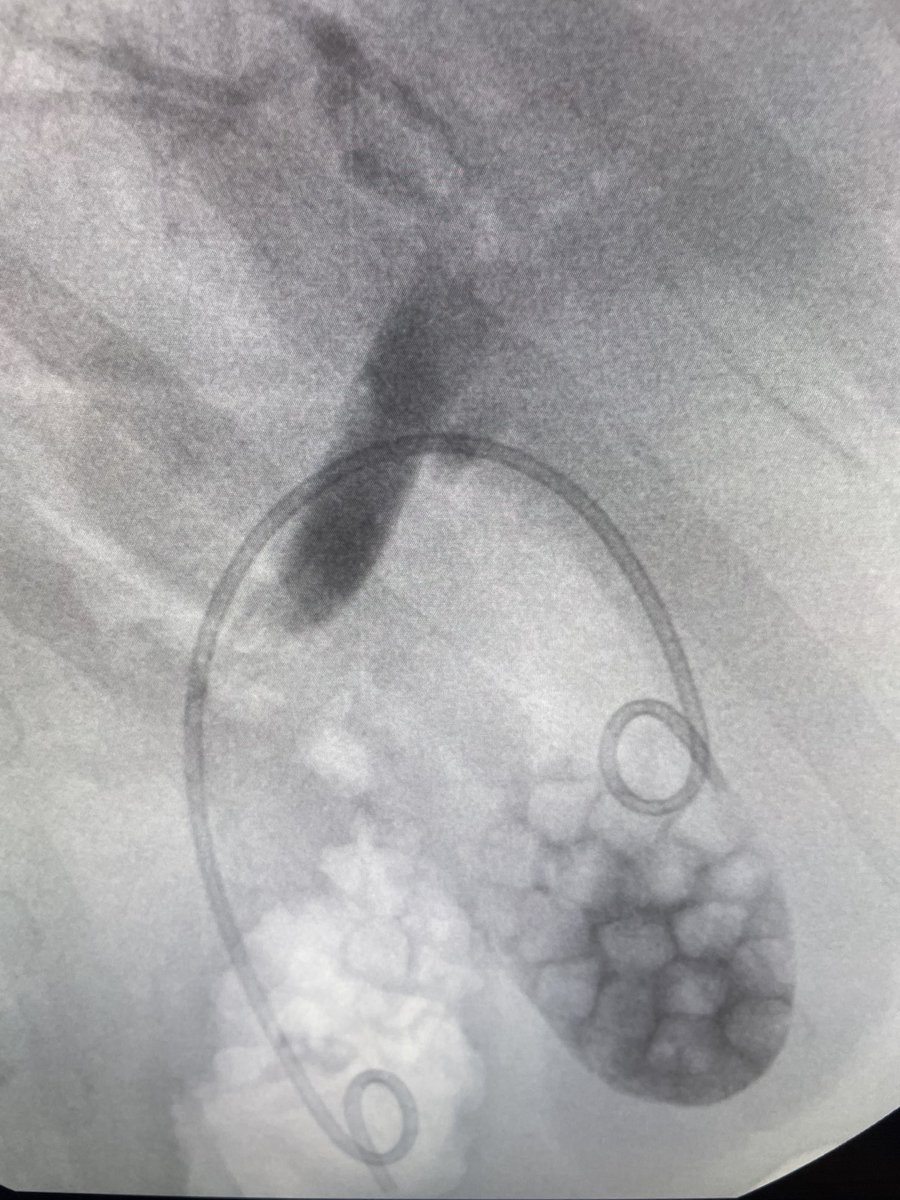

Such a honor to perform live endoscopy during our Annual Mellinkoff symposium @UCLA! Gastroplasty & sleeve revision as primary solutions for weight regain following

Bariatric surgery and #GLP1 RA 🏥